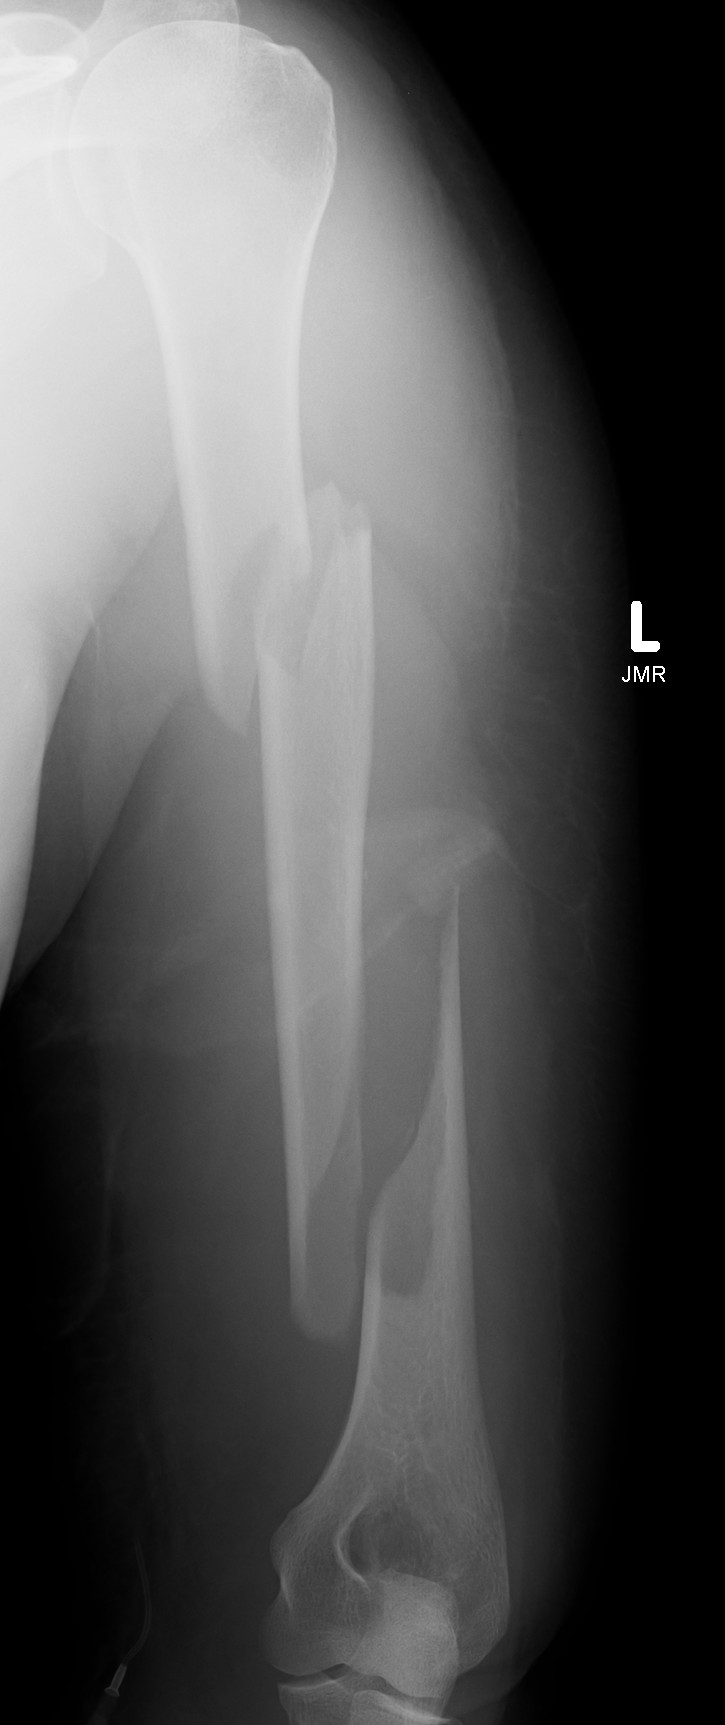

Holstein Lewis fracture

Holstein Lewis fractureHolstein Lewis

Holstein-Lewis JBJS Am 1963

- series of 7 oblique distal third fractures with radial nerve injury

- all were treated operatively

- nerve in fracture gap in 2 / impaled in 1 / severed in 2 / contused +/- in callus in 2

- advised against attempted closed reduction

- risk of contusing nerve between fragments

- advised early open reduction through anterolateral approach

- the radial nerve is closely assoicated with the fracture site and the fracture spike